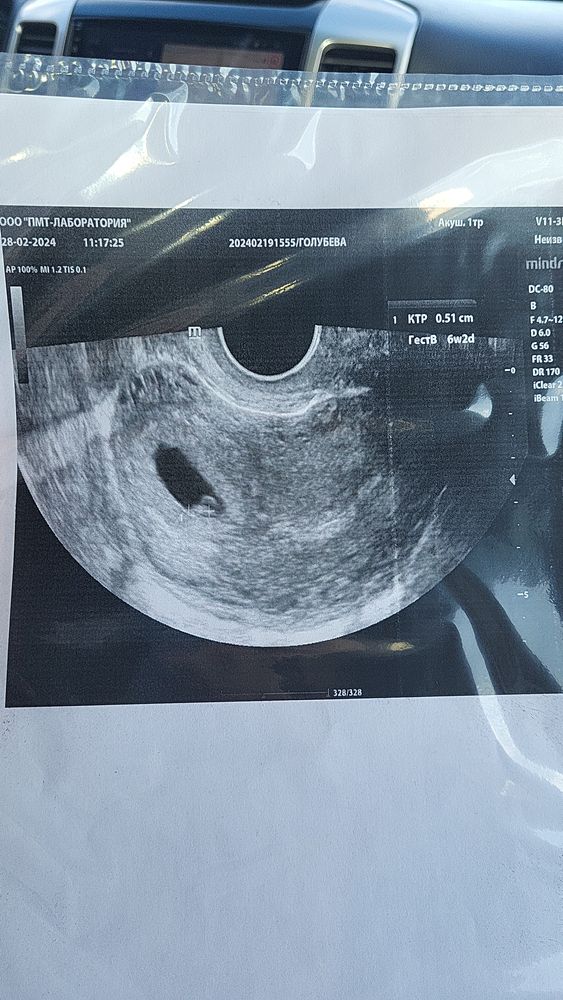

***, а по делу по КТР срок был 6 недель 6 дней и ЧСС 116, ничего подобного мне не писали

Срок 7 недель. Чсс 129. Не переживайте все отлично! Если очень тревожно переделайте уши в другом месте!

если у вас овуляция не отслежена, то вполне возможно что у вас срок 6+2 и чсс так же норма для этого срока. Опять же со временем всё сравняется, пока крошка маленькая, будет небольшой разброс

В учебнике написано, что брадикардия ниже 100 Уд в минуту, мне Г раньше говорила, что ниже 110 не оч хороший признак, а у Вас, по-моему, всё нормально